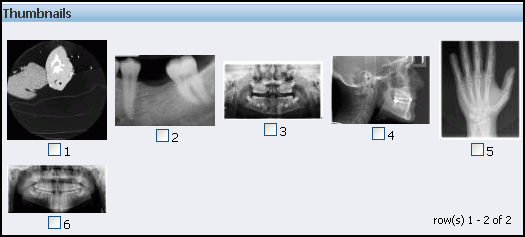

Figure 6-3 shows the Thumbnails area, which contains six thumbnail images representing the DICOM images that are installed with the sample application.

Figure 6-3 Thumbnails Area on the DICOM Image Archive Home Page